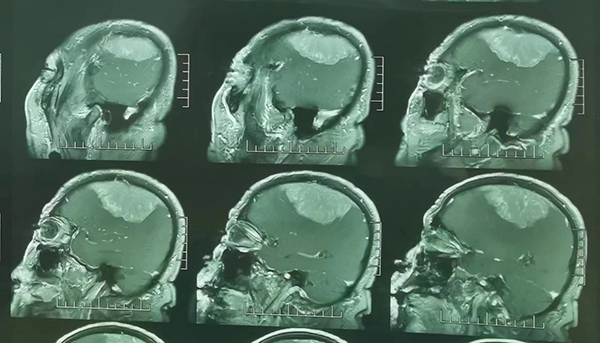

2周前,家住沛縣的劉老先生逐漸覺得左側(cè)胳膊腿有些麻木,開始以為年紀(jì)大了,有點(diǎn)輕微腦梗,也沒過多在意,可是后來癥狀越來越重,家里子女不放心,就帶他到當(dāng)?shù)蒯t(yī)院做了個檢查。不查不要緊,一查嚇一跳,CT和MR發(fā)現(xiàn)劉老先生顱內(nèi)長了一個接近10cm的瘤子。當(dāng)?shù)蒯t(yī)生馬上介紹他到徐醫(yī)附院顱底腫瘤外科。

苗發(fā)安副主任醫(yī)師接診后,安排劉老先生住院進(jìn)一步完善了相關(guān)檢查,結(jié)果發(fā)現(xiàn)劉老先生顱內(nèi)長了一個大小約10cm*8cm大小的腦膜瘤。腫瘤不僅僅體積大,位置也不好,壓在了右腦的運(yùn)動區(qū),術(shù)后很可能會出現(xiàn)左側(cè)肢體偏癱等并發(fā)癥。診斷明確后顱底腫瘤外科主任范月超教授、梁君主任醫(yī)師組織科室進(jìn)行了手術(shù)方案的討論,結(jié)合患者年齡、癥狀,腫瘤大小、位置等,制定了周密的術(shù)前準(zhǔn)備和手術(shù)方案。